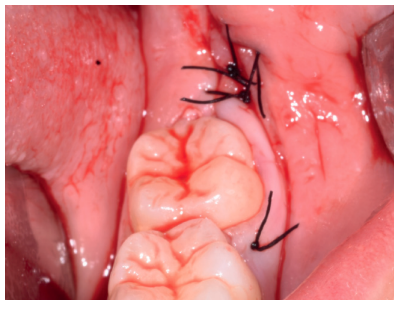

Los fragmentos coronal y radicular procedentes del tercer molar inferior y del premolar superior se limpiaron de restos de tejidos blandos y, secos, se introdujeron en la máquina Smart Dentin Grinder® (Kometa Bio, BIONER, España), tal y como aparece en la Figura 14. Tras un ciclo de triturado de 3 segundos, y otro de tamizado de 20 segundos, el material obtenido se limpió con la primera solución durante 12 minutos, y después durante 3 minutos con la segunda solución (Figura 15), para después transportar el material de injerto al alveolo, con presión controlada (Figura 16). Una vez compactado, se colocó una membrana de colágeno (Figura 17) y se suturó la herida con seda de 4/0, mediante puntos periodontales en las papilas (Figura 18). Se realizó una radiografía panorámica en el postoperatorio inmediato (Figura 19).